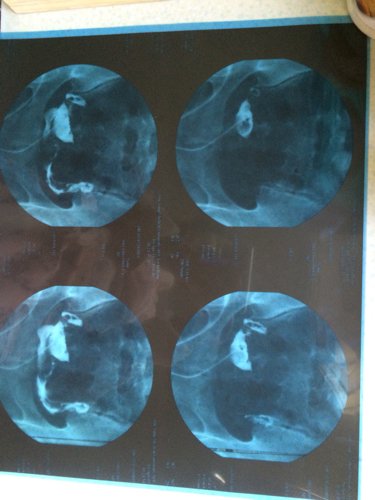

麻烦看看图,检查结果显示双侧输卵管通畅,但是医生看了片说通畅得不好,很难自然怀孕,要求做宫腔镜手术 麻烦看看图,检查结果显示双侧输卵管通畅,但是医生看了片说通畅得不好,很难自然怀孕,要求做宫腔镜手术,这什么情况呀? 点击展开 494317348 2015-05-01 18:51 为您推荐: 其他回答 通畅。建议在两次月经之间那几天爱爱比较容易受孕。还要检查男方是不是精子也正常才行。 匿名用户 2015-05-01 20:09 准备坑你钱了 匿名用户 2015-05-01 19:01 这是手术里面的 匿名用户 2015-05-01 18:52 相关问题 请问做宫腔镜检查都是好的!输卵管口也是清晰可见是不是说明输卵管也是通的?有图!麻烦懂的人帮忙分析一 怀孕五个月,发现右肾结石,医生建议保守治疗,建议多喝水自然排石,问题是如果长时间自然排石不成功对孕 我想问下医生如果子宫有炎症,怀孕了是不是查不出来,麻烦专业医生回答,谢谢